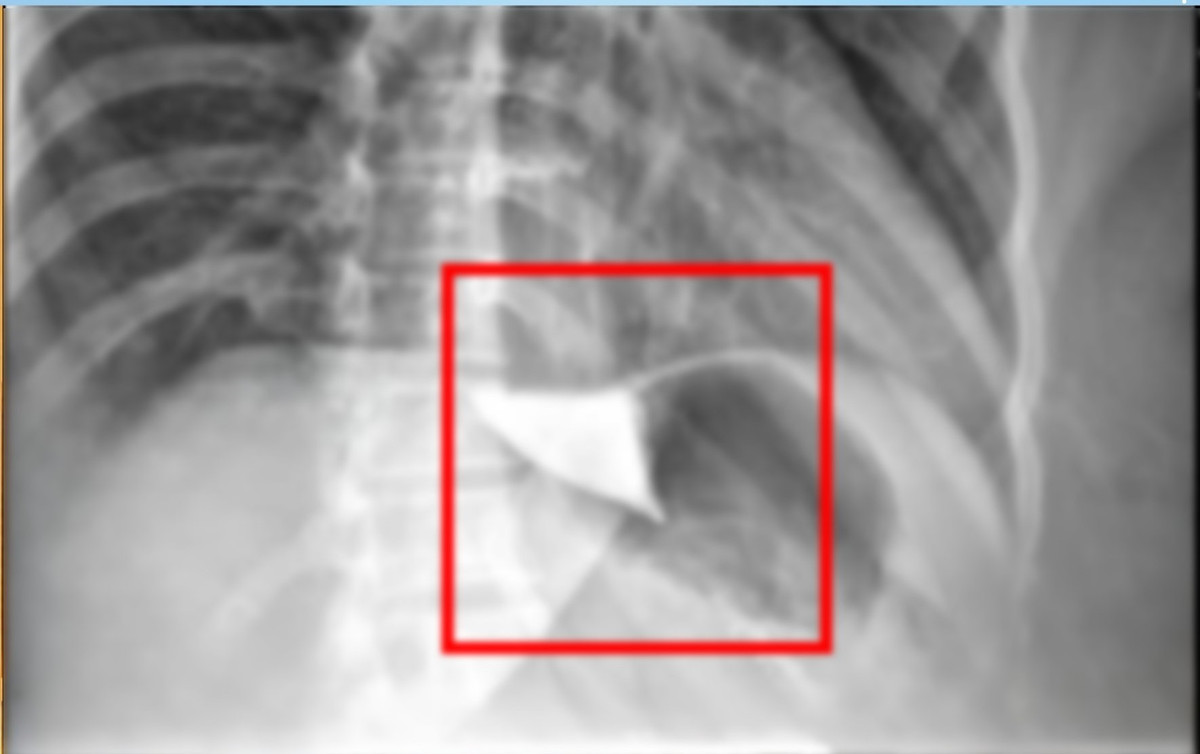

Ngày 07/10/2025, sau khi nhập viện tại Bệnh viện Đa khoa Thủ Đức, chị H được thực hiện các thăm khám lâm sàng, nội soi, xét nghiệm cận lâm sàng và chụp CT. Sau đó, bệnh nhân được chỉ định phẫu thuật Heller kết hợp tạo hình tâm vị theo phương pháp Dor.

Tạo hình thực quản - Ảnh BVCC